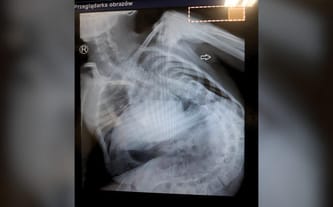

W potrzasku własnego ciała. RATUNKU!

Fundraiser goal: Przystosowanie wózka inwalidzkiego, leczenie i rehabilitacja

Choroby neurologiczne